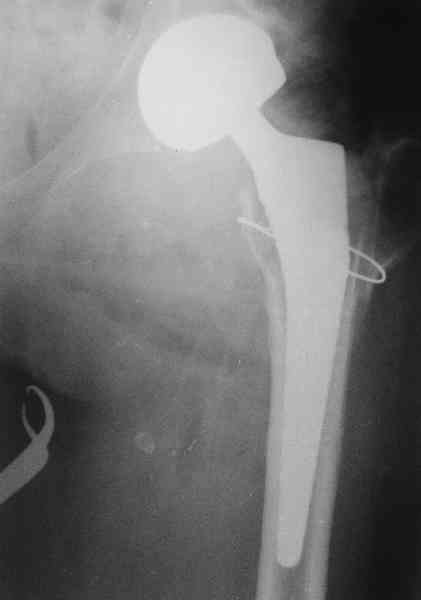

Не такое уж страшное укорочение по снимкам.Вчера прооперирован похожий случай.Обошлись без релиза и аппаратного низведения. укорочение было 4 сантиметра.Теперь ножки ровные.